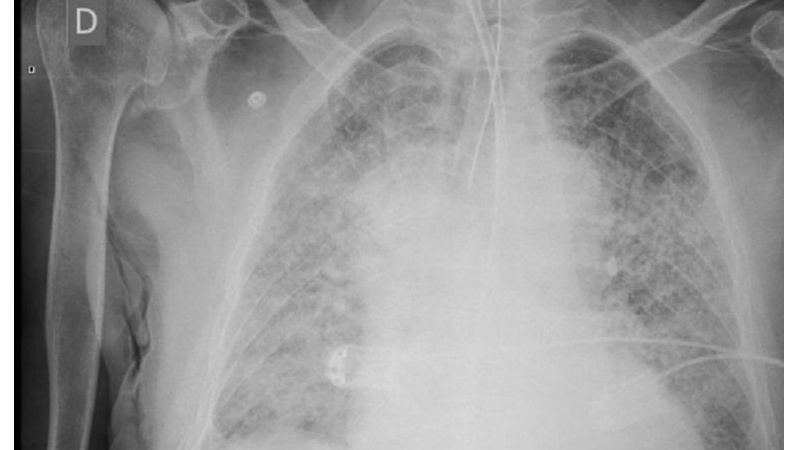

BUENOS AIRES-Una misteriosa polmonite (non è Covid) in Argentina ha finora colpito 10 persone, tre delle quali sono morte.

Sono nove in tutto i pazienti ai quali è stata diagnosticata. L’Oms sta monitorando l’epidemia.

La polmonite di origine sconosciuta si è manifestata a Tucuman, nell’Argentina nord-occidentale, ha provocato la sua quarta vittima in meno di una settimana. L’annuncio è stato dato dal ministero della Sanità della provincia.

“Si tratta di un paziente di sesso maschile, di 48 anni, che presentava delle comorbidità ed era ricoverato in gravi condizioni”, ha precisato il ministero della Sanità di Tucuman.

Finora, tutti i casi sono collegati a una clinica. Precedentemente sono morti due operatori sanitari e un paziente della clinica. Una donna di 70 anni, operata nella struttura, è stata individuata e curata come “paziente zero”.

Hector Sale, presidente del collegio medico provinciale di Tucuman, ha affermato che al momento non ci sono prove conclusive di trasmissione da persona a persona perché non ci sono stati casi tra coloro che sono in stretto contatto con nessuno dei pazienti.